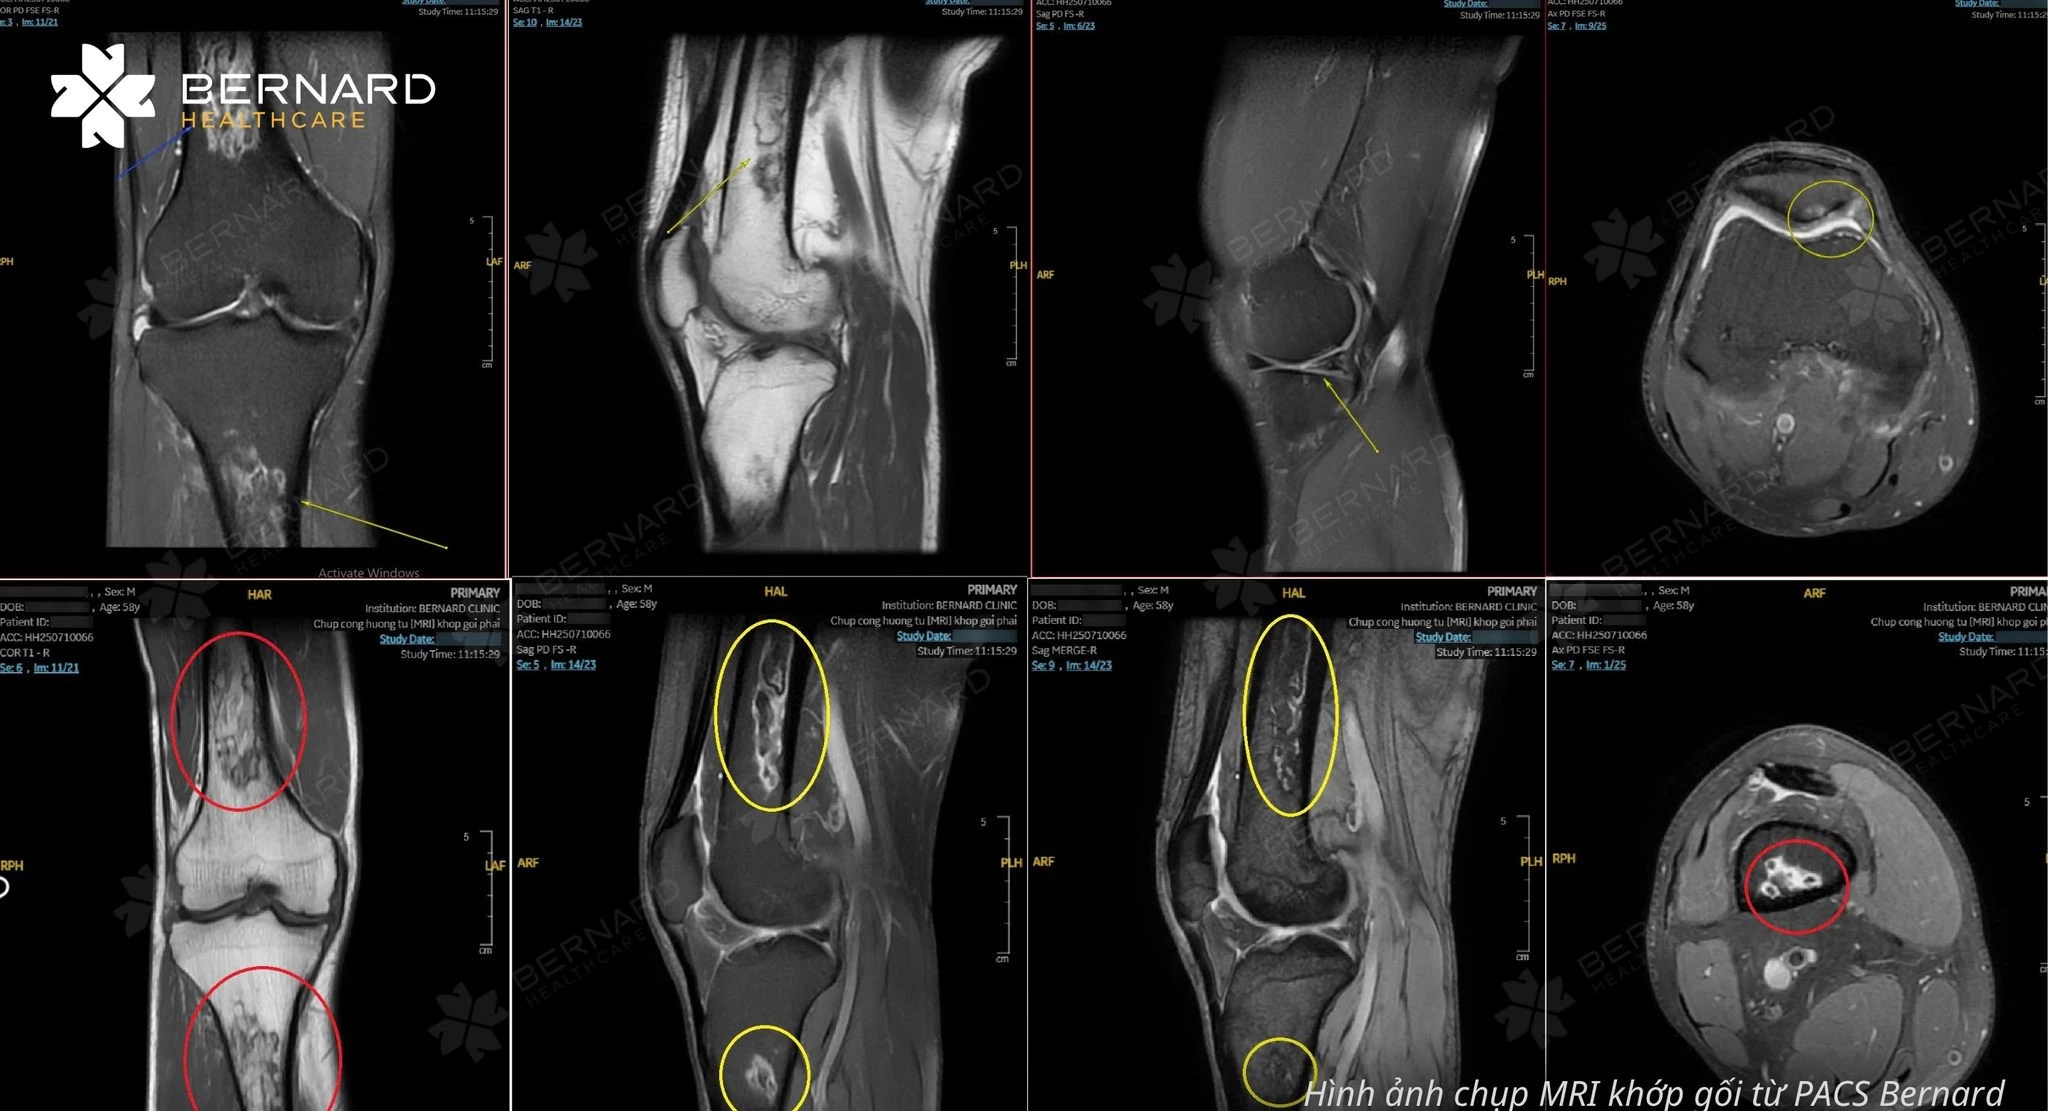

Trước biểu hiện trong không điển hình và nguy cơ bỏ sót tổn thương sâu trong khớp, bác sĩ chỉ định MRI khớp gối nhằm đánh giá toàn diện cấu trúc bên trong. Kết quả ghi nhận nhiều tổn thương phối hợp: tổn thương xương dưới sụn, thoái hóa sụn chêm, tổn thương sụn khớp kèm thay đổi mô mềm và nang Baker vùng khoeo.

Theo TS.BS.CK2 Nguyễn Đại Hùng Linh – Phụ trách Chuyên khoa Chẩn đoán hình ảnh Bernard Healthcare, đây là những tổn thương có thể tiến triển âm thầm và rất dễ bị bỏ sót nếu chỉ dựa vào thăm khám ban đầu hoặc các kỹ thuật chẩn đoán hình ảnh hạn chế trong đánh giá mô mềm.

Việc phát hiện sớm bằng MRI giúp bác sĩ đánh giá chính xác mức độ tổn thương, mối liên quan giữa các cấu trúc trong khớp, từ đó định hướng điều trị phù hợp và tăng khả năng bảo tồn chức năng vận động.